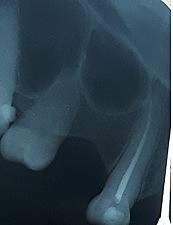

• Serie radiográfica

Serie radiográfica

Se realiza la toma de radiografías peri apical. Se observa pérdida ósea considerable así como ensanchamiento periodontal en OD 1.1 y 2.1.